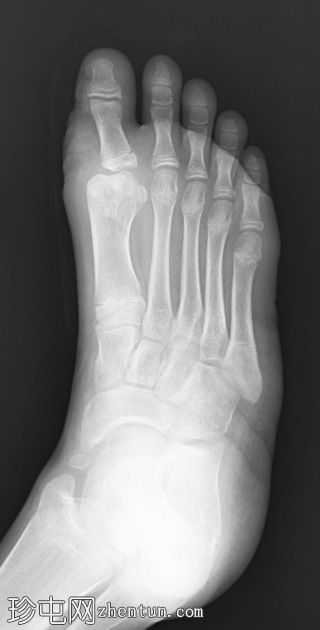

术后

X线片

正位片

侧位片

影像

显示足部骨骼排列正常;然而,第一跖跗关节处可见软组织肿胀,且第一跖骨增宽。这些特征与术后切除多余的轴前多趾畸形相符。